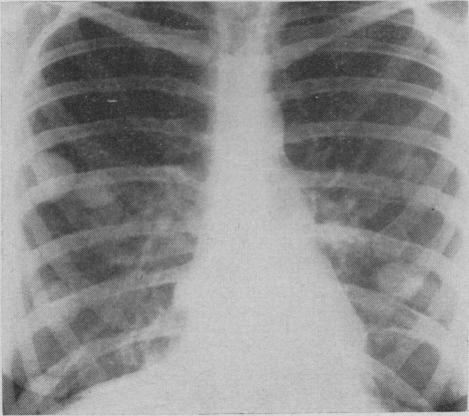

Pulmonary histoplasmosis.

Can Med Assoc J. 1959 Sep 15;81(6):486-8.